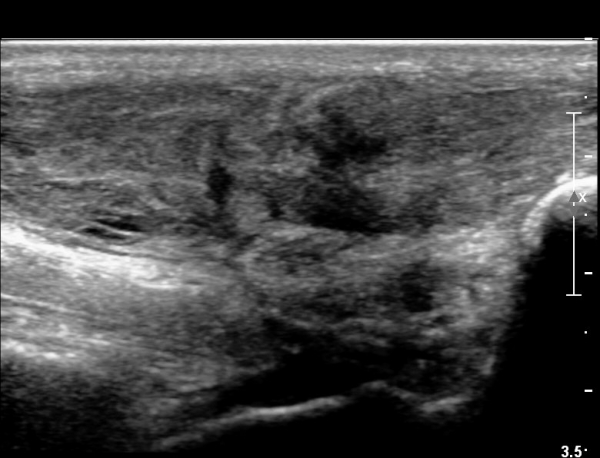

¾ÆÅ³·¹½º°Ç Á¾´Ü¸é°Ë»ç¿¡¼­ ¾ÆÅ³·¹½º°Ç ¸»´ÜºÎ¿¡ ¾ÆÅ³·¹½º°ÇÀÇ Àú¿¡ÄÚºÎÁ¾, ±¹¼ÒÀû ¿¬°á¼º ¼Ò½Ç,

¹ß¸ñ°üÀý ÈĹæºÎ¿¡ ¼ö¾×Àú·ù°¡ °üÂûµÊ(»çÁø 3, 4, 5).